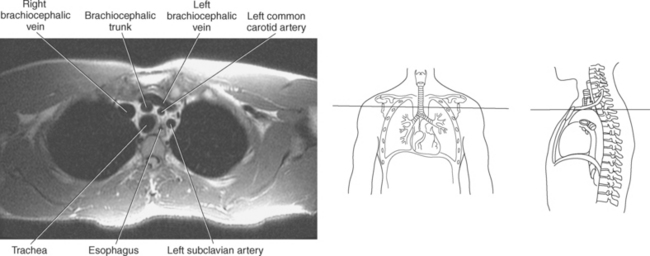

The three main branches of the aortic arch are the brachiocephalic trunk, left common carotid artery, and left subclavian artery (Figure 6.84). The brachiocephalic (innominate) trunk is the first major vessel and the largest branch arising from the aortic arch. It ascends obliquely to the upper border of the right sternoclavicular joint, where it divides into the right common carotid and right subclavian arteries (Figures 6.85 and 6.86). The right common carotid artery ascends the neck lateral to the trachea to the level of C4, where it divides into the right external and internal carotid arteries. The right subclavian artery curves posterior to the clavicle into the axillary region, where it becomes the right axillary artery. The left common carotid artery is the second vessel to branch from the aortic arch. It arises just behind the left sternoclavicular joint and ascends into the neck along the left side of the trachea to the level of C4, where it bifurcates into the left external and internal carotid arteries. The left subclavian artery arises from the aortic arch posterior to the left common carotid artery and arches laterally toward the axilla in a manner similar to that of the right subclavian artery, where it continues as the left axillary artery (Figures 6.85 through 6.88). The right and left internal thoracic arteries arise from the respective subclavian artery at the base of the neck. They run deep to the ribs, just lateral to the sternum, to supply blood to the anterior portion of the thorax (Figure 6.89). The common carotid arteries supply blood to the head and neck, whereas the subclavian arteries supply blood to the upper extremities.

The superior vena cava receives blood from the head and neck via the internal and external jugular veins and from the upper extremities via the subclavian veins (Figures 6.84 and 6.90). The subclavian veins arise from the axillary veins and course posterior to the clavicles. They receive blood from the external jugular veins before uniting with the internal jugular veins behind the sternoclavicular joints, where they continue as the brachiocephalic veins. The left brachiocephalic vein courses across the midline, anterior to the branches of the aorta, to unite with the right brachiocephalic vein just posterior to the costal cartilage of the right first rib. The union of the two brachiocephalic veins forms the superior vena cava, which empties into the right atrium of the heart (Figures 6.75 and 6.76).